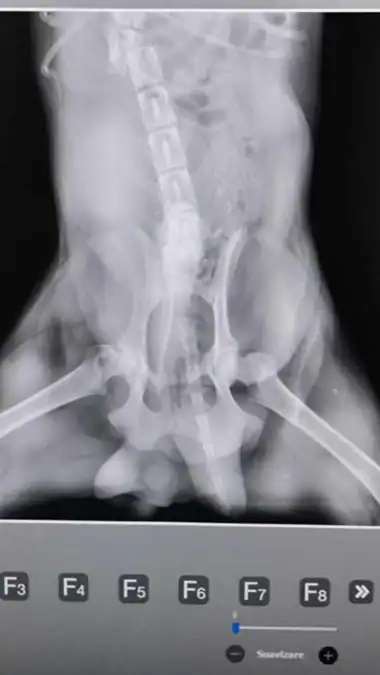

X rays revealed the truth.

Multiple fractures along his spine.

Damage that could steal his ability to walk.